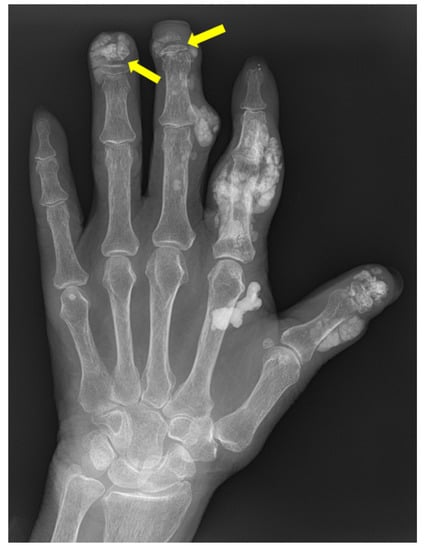

5. Psoriatic Arthritis (PsA)

8. Gout